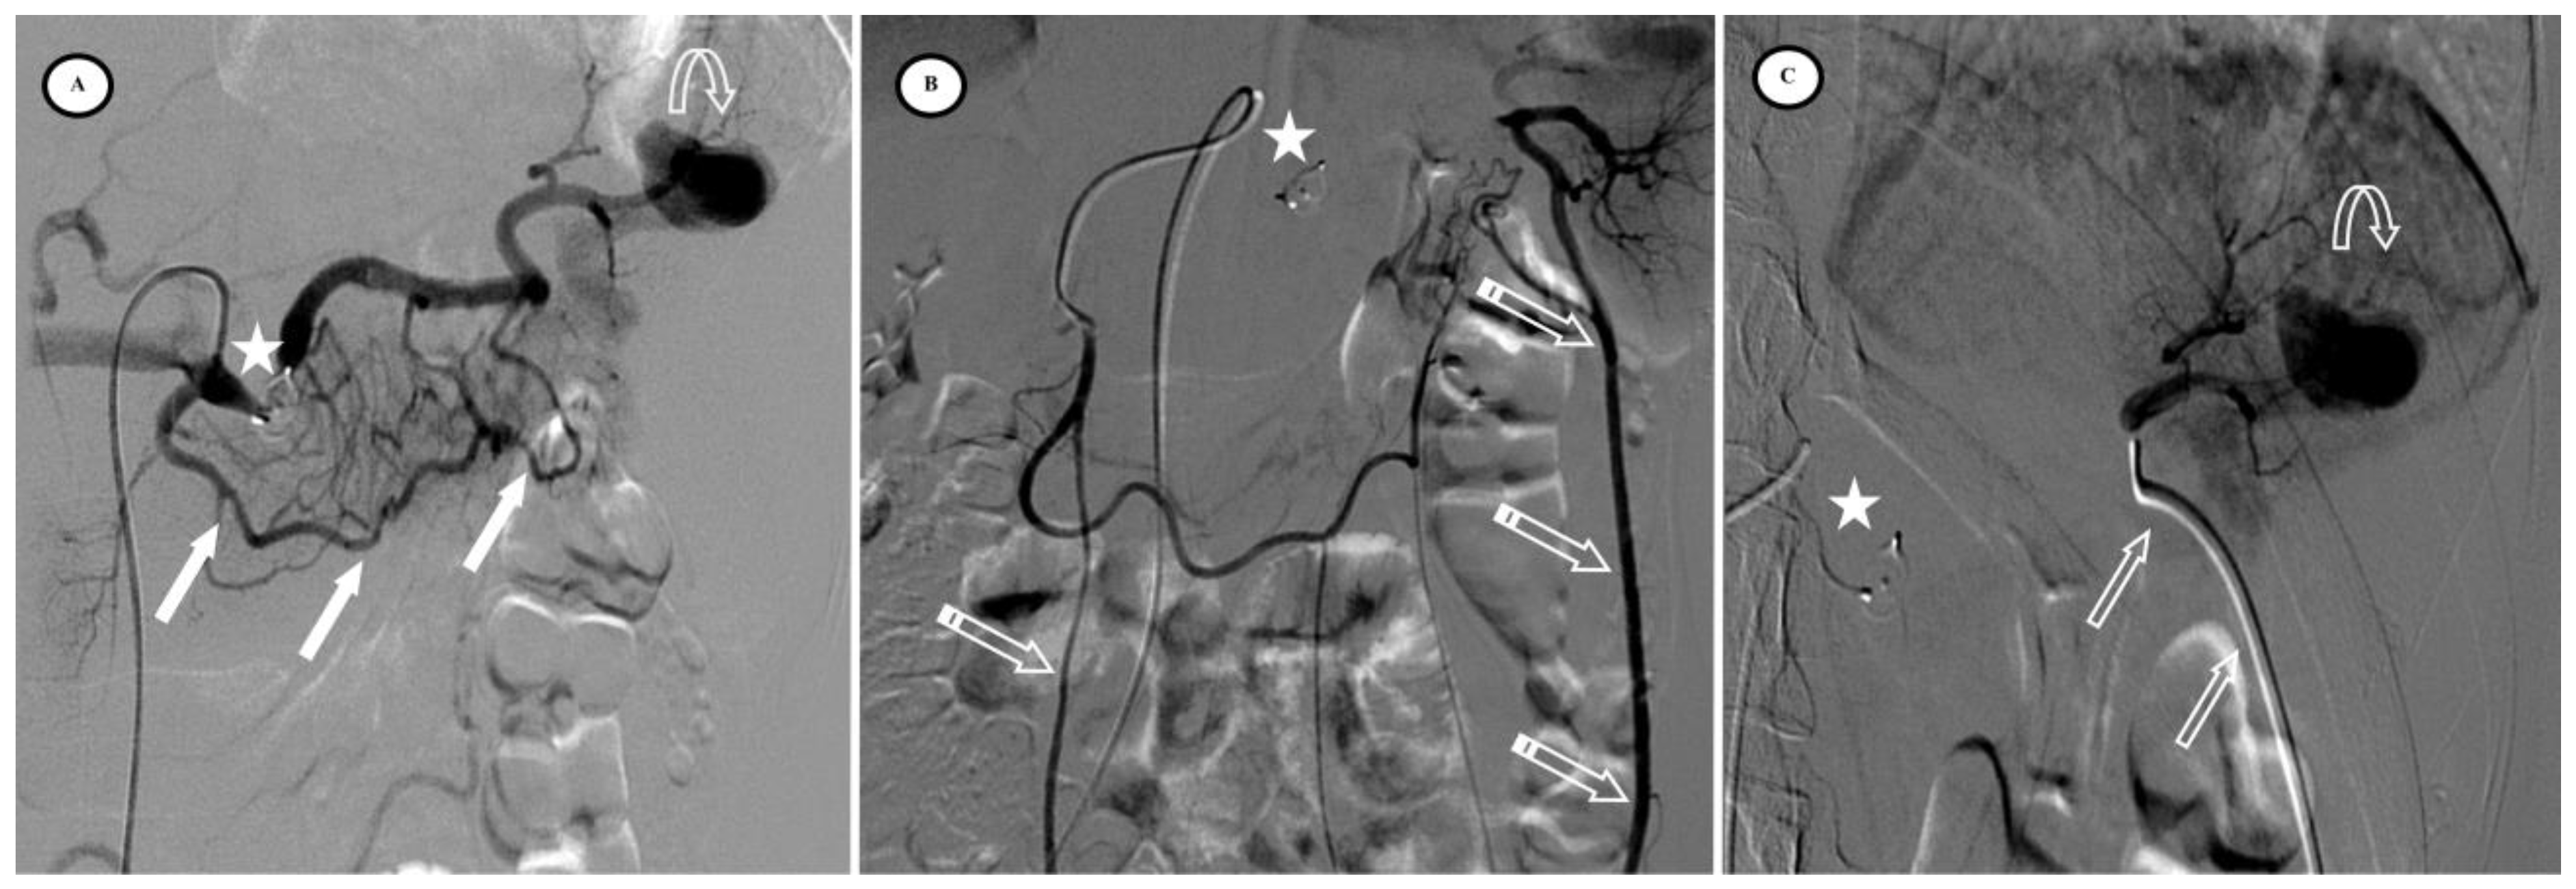

According to the SIR classification, no procedure-related Grade 3 or higher adverse events (AEs) existed. Mild AEs included puncture site hematoma (n = 2/57, 3.5%) and puncture site pain (n = 5/57, 8.7%). Primary efficacy was achieved in 97% of cases but two patients were re-embolized; one for active bleeding on Day 6 (Figure 4) and the other for an arteriovenous fistula on Day 30 (Figure 5). No deaths, rescue splenectomies, or hemorrhagic, infectious, or thromboembolic complications occurred. Secondary efficacy was high, with no cases of necrotic pancreatitis and a high splenic salvage rate (94.7%), as only three cases of < 50% vascularized spleen parenchyma were observed at the consultation on Day 30. The average percentage of vascularized spleens at one month was 86.7% (SD = 14.2%), with more vascularized parenchyma in the AVP group (p < 0.01).

Figure 5.

Secondary arteriovenous (AV) fistula development 30 days after preventive proximal splenic artery embolization (PPSAE). (A) shows PPSAE using Penumbra occlusion device (star), the subsequent development of collateral circulation mainly through the dorsal pancreatic artery and the great pancreatic artery (blank arrows), and the secondary AV fistula (arrow). (B) illustrates the distal microcatheter selection (striped arrow) through radial access. (C) shows microcoil embolization (blank star) with satisfying angiographic results.